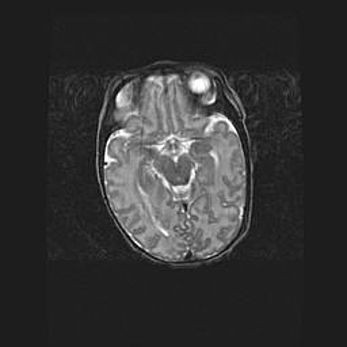

Подострая гематома правой гемисферы мозжечка.

Наружная гидроцефалия.

Возраст: 15 дней

Вес: 3100 г

Пол: женский

Окружность головы: 37 см

Срок гестации: 35-36 недель

При открытой наружной форме гидроцефалии у новорожденных расширяются и переполняются субарахноидные пространства.

Кровоизлияния в мозжечок имеют две клинико-анатомические формы: полушарные гематомы и кровоизлияния в червь.

К появлению этой патологии может привести: повреждения головного мозга, возникающие в результате асфиксии и гипоксии плода при беременности, или травмы во время родов. Редко гематома мозжечка может быть результатом первичной коагулопатии и сосудистой мальформации, диссеминированном внутрисосудистом свертывании, изоиммунной тромбоцитопении.